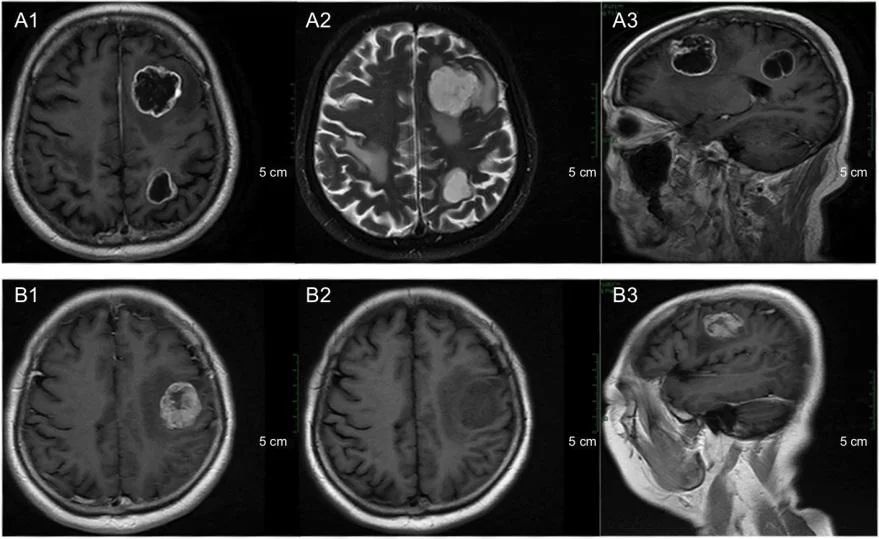

Απεικονιστικές μελέτες – Η μαγνητική τομογραφία (MRI) είναι η προτιμώμενη μελέτη απεικόνισης για τη διάγνωση εγκεφαλικών μεταστάσεων (εικόνα 1) Η μαγνητική τομογραφία είναι πιο ευαίσθητη από την αξονική τομογραφία (CT) στην ανίχνευση βλαβών σε ασθενείς που υποπτεύονται ότι έχουν εγκεφαλικές μεταστάσεις.

Παρακολούθηση: Οι μεταστάσεις του εγκεφάλου θα πρέπει να ακολουθούνται με μαγνητική τομογραφία (MRI) για την ανίχνευση πρώιμων ενδείξεων υποτροπής ή νέων βλαβών.

Συνήθως επαναλαμβάνουμε τη μαγνητική τομογραφία ένα μήνα μετά την αρχική θεραπεία και στη συνέχεια επαναλαμβάνουμε την απεικόνιση κάθε τρεις μήνες.